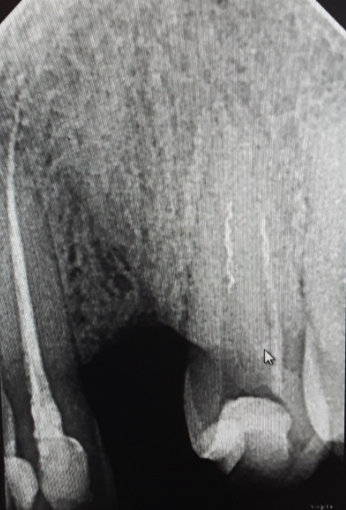

Вчера был у стоматолога, делали снимок, на снимке сказали с зубом все хорошо и не стали ничего с ним делать, выписали противовоспалительные препараты. Сказали, если до понедельника боль не пройдёт, будут удалять пломбу. Боль не проходит, отдаёт в щеку. За день до того как заболел зуб, пил холодную воду. Зуб шестёрка.

После пломбирования каналов зуба возможно воспаление периодонта, причинами могут быть:

Одним из признаков воспаления периодонта является болезненность при накусывании на зуб.